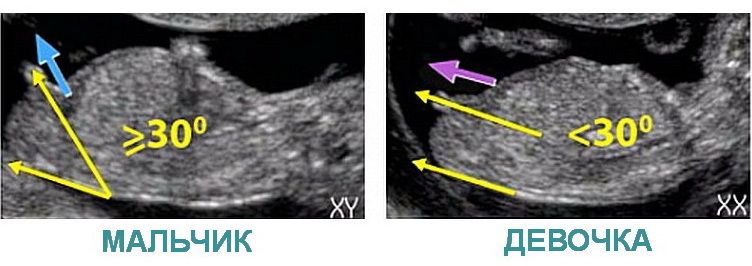

Аня, если верить интернету, то как то так 😁😁 Изображение

06.11.2022

Аня, тогда на каком основании врач уверен, что у вас мальчик?

Так это ещё половой бугорок. Мне кажется у вас девочка.

Olga dey, так оно и есть. Был виден половой бугорок, на сроке 13 недель одинаковый и у мальчиков и у девочек